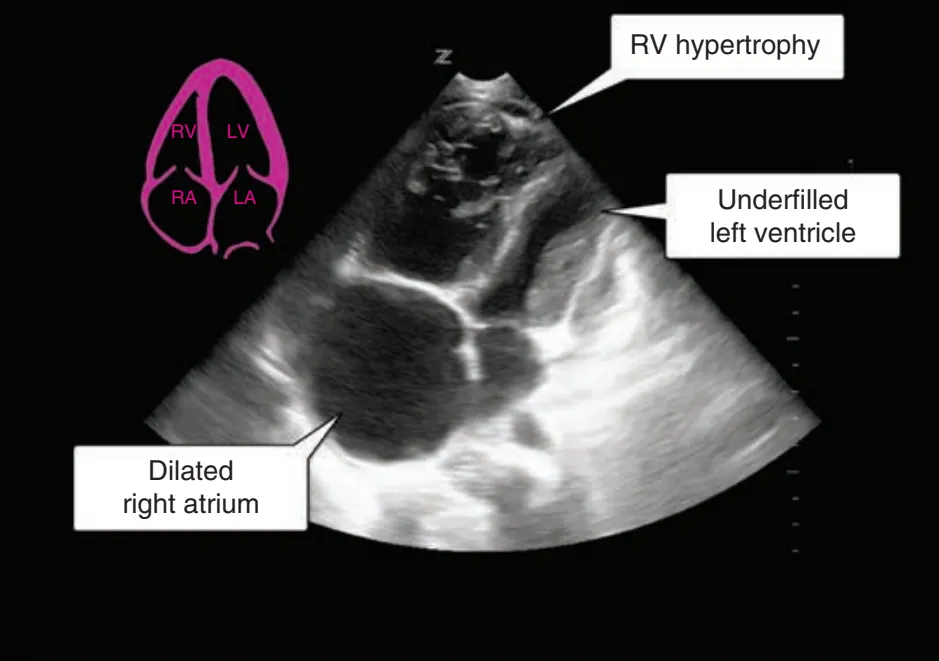

: RV hypertrophy, TR, RV function 저하 (아래 그림 소견 및 TRvmax, TAPSE, IVC size 등으로 의심)

심한 경우 : Septal deviation, RV-to-left ventricle end-diastolic diameter >1 in AP4C view

AP4C view. RV가 확장되어 있으면서 RV trabeculae가 두꺼워져 있는데, 이는 RV의 만성적인 overload를 시사한다. 수축기에 IVS도 LV 쪽으로 치우쳐져 있어, RV Pressure oveload를 시사한다. 정상 AP4C view는 좌상단에 표시되어 있다.